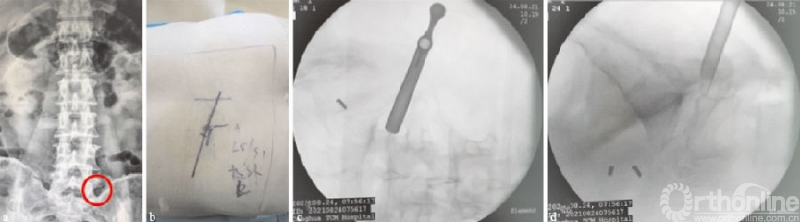

一般除了L5S1节段外,经典的YESS穿刺技术是首选方案,而对于突出位于神经根前方或内侧方向的,可综合测量CT、MR与突出物位置的距离、角度,进行靶点穿刺。在L5S1节段,术前要考虑患者腰骶角、横突、髂骨、椎间盘突出的位置等情况[14],如L5横突粗大造成L5S1横突间距狭窄的,建议行关节突成形或用镜下磨钻来扩大空间,以利于工作通道置入(见图3)。

(a)腰椎正位X线片示左侧横突粗大;(b)穿刺点距离及穿刺方向规划图;(c)(d)工作通道放置X线透视图;○指狭小的工作通道空间

图3 L5S1节段左侧极外侧突出穿刺点及置管图